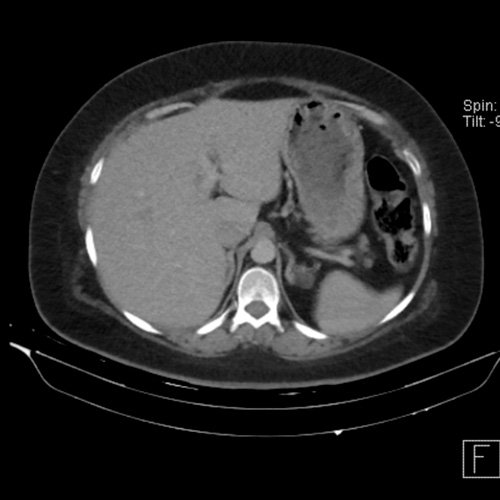

• Tomografía de abdomen y pelvis sin contraste oral con contraste EV (12/02/26):  El hígado es de forma, tamaño y situación habituales. Su superficie es lisa, y sus bordes son agudos. Imagen hipovascular aislada de 15 mm en segmento V de aspecto inespecífico. Sugiero complementar con RMI. La vía biliar intra y extrahepática es de calibre conservado. La vesícula biliar es de forma, tamaño y situación normales, sin imágenes que sugieran la presencia de litiasis. Tener en cuenta que este método puede pasar por alto litiasis colesterínicas. El bazo es de forma, tamaño y situación normales. El páncreas es de características normales. El conducto de Wirsung es de calibre conservado. Adenoma adrenal izquierdo de 16 mm. Ambos riñones son de forma, tamaño y situación habituales. Concentran y eliminan adecuadamente la sustancia de contraste. Sin evidencia de alteraciones calicopiélicas ni ureterales. La aorta, las arterias ilíacas primitivas, internas, externas y femorales, son de calibre y trayecto conservado, permeables. La vena cava inferior y las venas ilíacas primitivas, internas, externas y femorales son de calibre y trayectoria conservados, permeables. No se observan adenomegalias intraperitoneales, retroperitoneales, ilíacas ni inguinales. No se observan alteraciones a nivel del tracto gastrointestinal. La vejiga es de paredes lisas, sin presentar efectos de masa endoluminales ni parietales. Utero en AVF, lateralizado a izquierda. Pequeña hernia umbilical de contenido graso y escaso líquido intrasacro. No se identifican alteraciones en las estructuras óseas visualizadas.

TC de abdomen y pelvis con contraste endovenoso (12/02/2026) Corte axial: hígado de forma, tamaño y situación habituales, con superficie lisa y bordes agudos.  Imagen hipovascular aislada de 15 mm en segmento V de aspecto inespecífico.

TC de abdomen y pelvis con contraste endovenoso (12/02/2026) Corte coronal: hígado de forma, tamaño y situación habituales, con superficie lisa y bordes agudos.  Imagen hipovascular aislada de 15 mm en segmento V de aspecto inespecífico.

TC de abdomen y pelvis con contraste endovenoso (12/02/2026) Corte sagital: hígado de forma, tamaño y situación habituales, con superficie lisa y bordes agudos.  Imagen hipovascular aislada de 15 mm en segmento V de aspecto inespecífico.